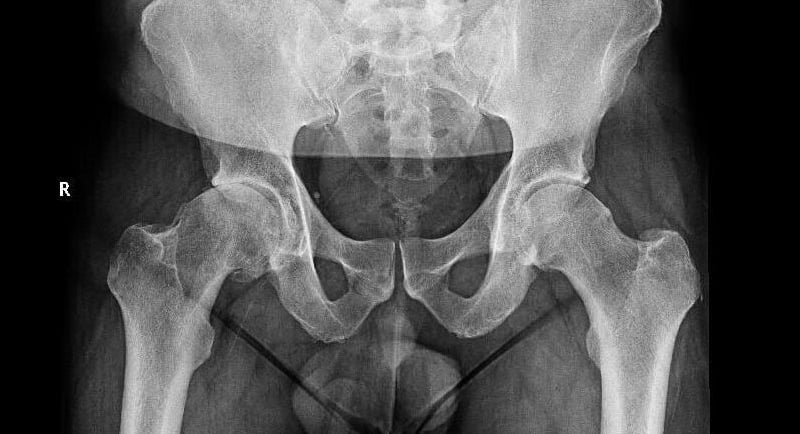

Diagnóstico

El diagnóstico se basa en una historia clínica detallada, la exploración física y estudios de imagen.

Las radiografías permiten observar el grado de desgaste del cartílago y la forma de la articulación.

En algunos casos, se pueden solicitar resonancia magnética o tomografía para evaluar estructuras blandas o alteraciones más sutiles.